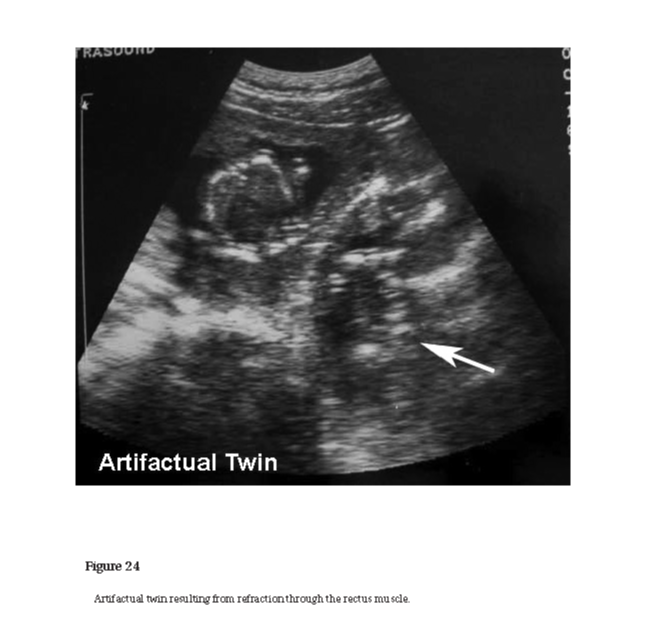

artifact

An anomaly in an ultrasound image that does not correspond to an actual anatomical structure or target. Artifacts can manifest as additional echoes, distortions, or missing information due to the interaction of ultrasound waves with tissues or structures. Reverberations and shadowing are examples of such artifacts (see Figures 15, 16, 21, 22, 23, and 24).

Figure 15 Figure 16 Figure 21 Figure 22 Figure 23 Figure 24